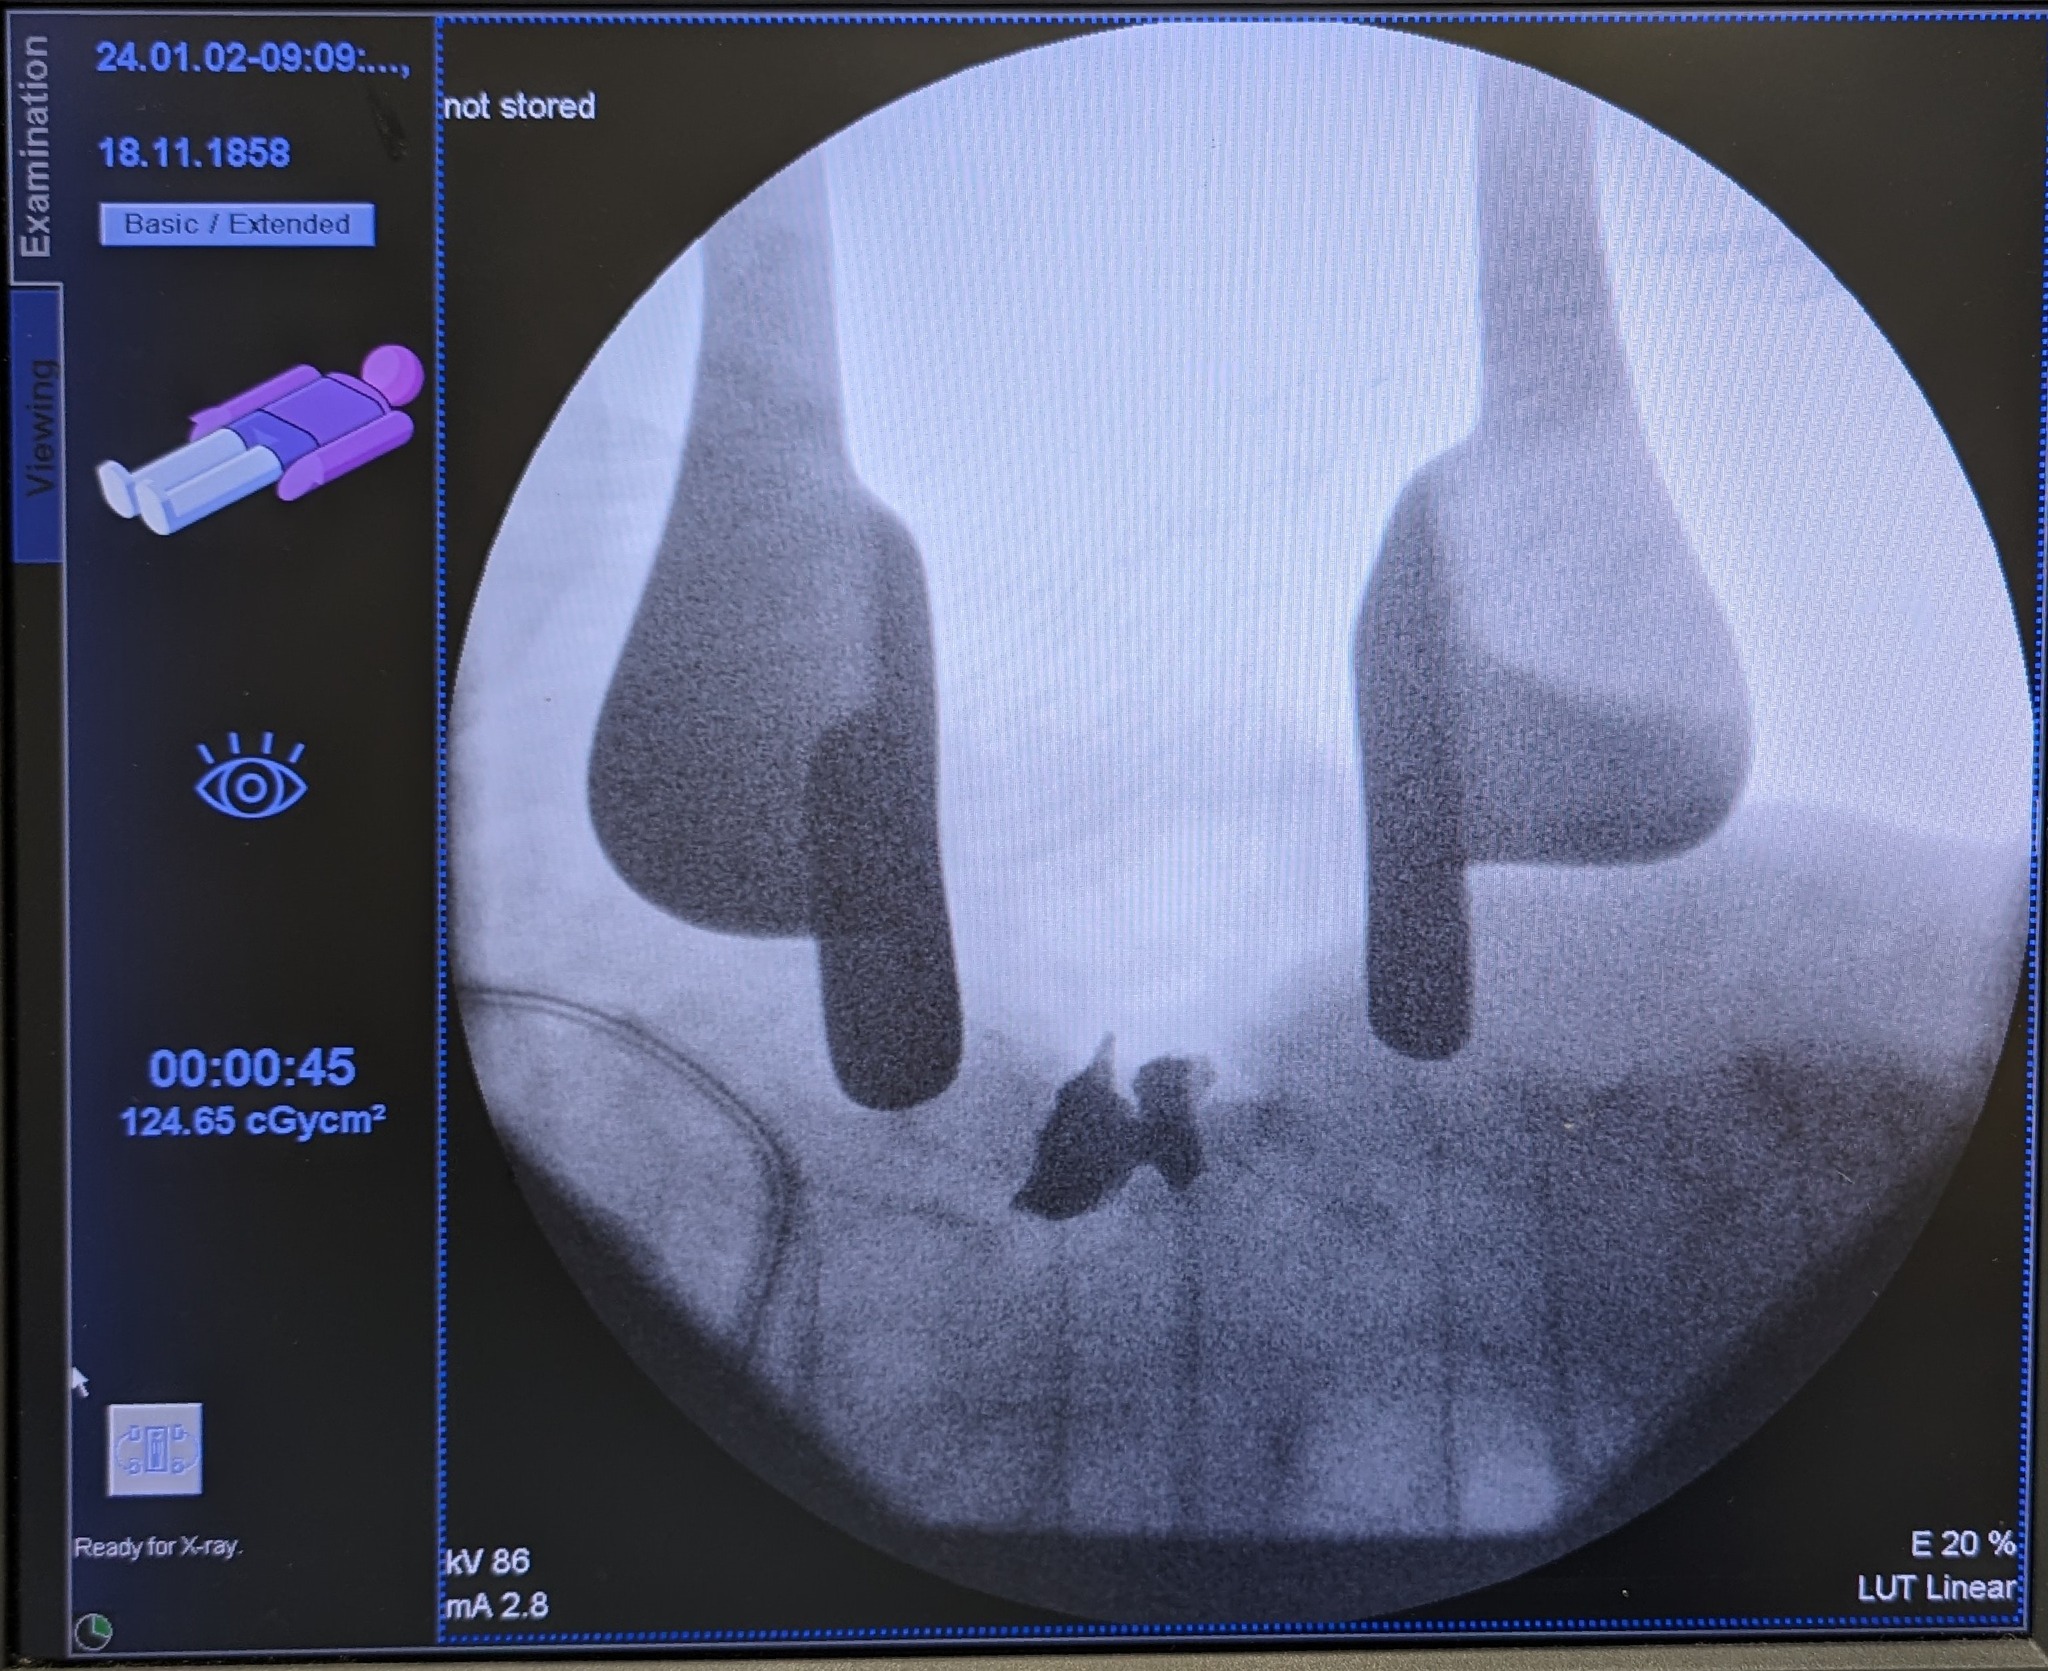

Благодаря компьютерной томографии (КТ) и электронно-оптическому преобразователю обломок был четко локализован. Это дало возможность провести точечную операцию по удалению куска металла.